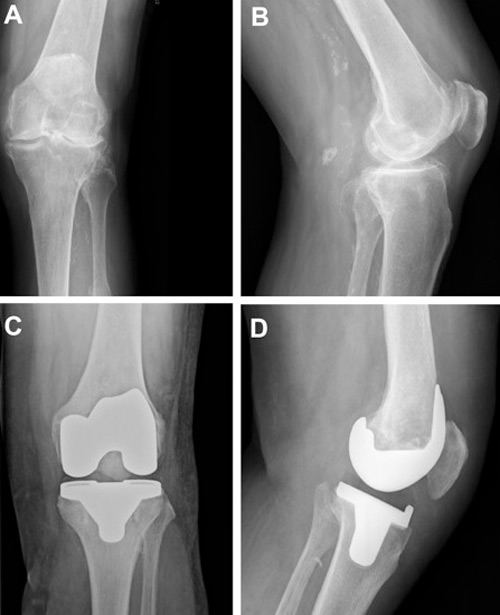

Figure 4

A. Anteroposterior X-ray of tricompartmental osteoarthritis. B. Lateral X-ray of tricompartmental osteoarthritis. C. Anteroposterior X-ray following total knee arthroplasty (TKA). D. Lateral X-ray following TKA.

The first prosthesis designed to replace all three knee compartments was introduced in 1972 by John Insall. Described as the “total condylar prosthesis”, it achieved very good outcomes and had a huge impact on condylar arthroplasty [35, 36]. Since then, there has been a remarkable increase in the number of TKAs performed annually. In the USA alone, over 700,000 TKAs were performed in 2011, a figure that is expected to increase by more than 600% by 2030 [37]. Figure 4 shows a radiograph of an arthritic knee before and after knee replacement.